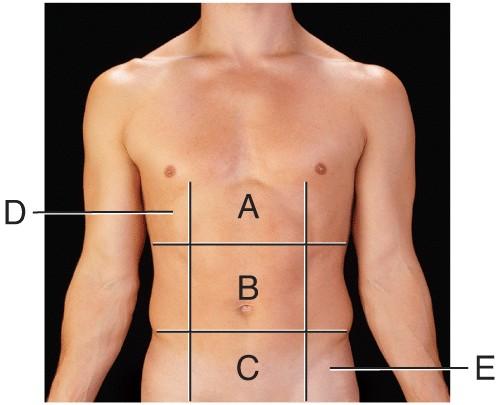

Name the region B.

middle hypochondriac

hypogastric

epigastric

Umbilical

Umbilical

Name the region A.

epigastric

umbilical

right hypochondriac

hypogastric

epigastric

Name the region E.

left hypochondriac

right lumbar

epigastric

left iliac

left iliac

Name the region C.

middle iliac

epigastric

umbilical

hypogastric

hypogastric

Name the region D.

Right Hypochondriac

Left Hypochondriac

epigastric

Right Lumbar

Right Hypochondriac

The liver is found in the region labeled:

A